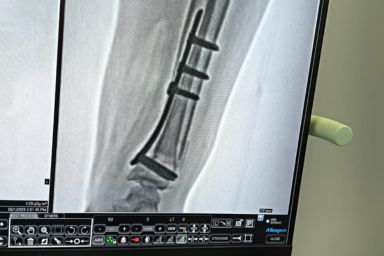

Advanced Orthopaedic Care with Modern OT Facilities by Dr S R Panda

Dr S R Panda is a reputed orthopaedic surgeon in Kolkata offering advanced facilities including General & Joint Replacement OT, Arthroscopy & Trauma OT, and Spine Surgery & Sports Injury OT, ensuring precise diagnosis, modern surgical techniques, and comprehensive bone and joint care under one roof.

Arthroscopy & Trauma OT